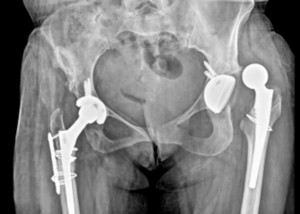

Welcome to Unmesh Clinic, home to Dr. Atul Ashok Patil, the Best orthopedic surgeon in Pune, renowned for excellence in orthopedic trauma surgery. Led by Dr. Patil, our clinic is dedicated to delivering personalized and advanced care for all kinds of bone and joint conditions. We specialize in treating complex orthopedic issues with procedures such as Anterior Cruciate Ligament (ACL) repair, Knee Pain Management, Robotic Joint Replacement, Pelvic-Acetabular Fracture Repair, and Total Knee & Hip Replacement (THR). Our goal is to ensure accurate diagnosis and effective treatment to help patients recover mobility and return to their active lives.

At Unmesh Clinic, Pune, we focus on offering the latest in minimally invasive fracture surgeries and management of complex intra-articular fractures, delayed unions, and non-union fractures. Our team combines surgical expertise with compassionate care to ensure every patient receives the best possible outcome. Explore our website to learn more about our orthopedic services, book appointments, and consult with us securely online. As a leading orthopedic trauma clinic in Pune, we are committed to your recovery, mobility, and long-term orthopedic health under the expert care of the Best orthopedic surgeon in Pune.